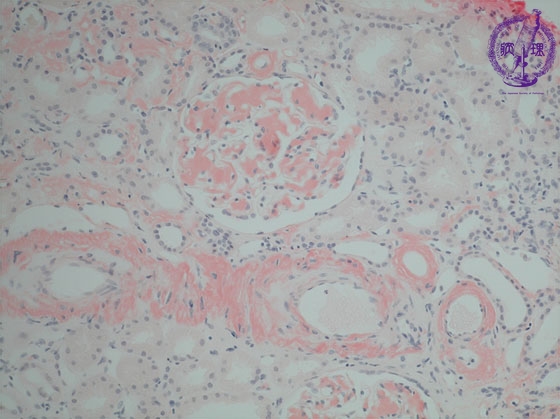

- ★(15)Renal amyloidosis

Microscopic findings ( Congo red, middle power view): Amyloid is (yellow dotted lines) stained orange color with Congo red stain.